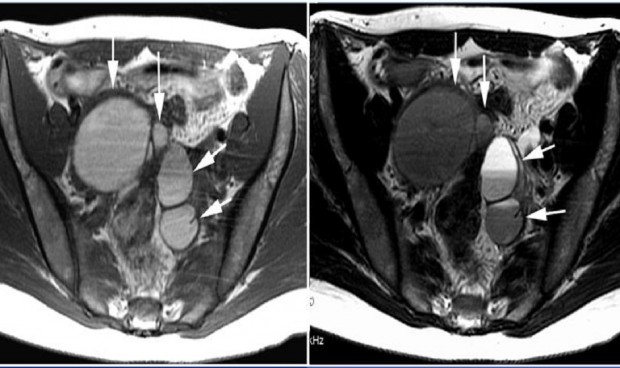

La eficacia y seguridad de la escleroterapia guiada por ultrasonido en Estados Unidos para el tratamiento del endometrioma ovárico mediante una revisión sistemática y un metanálisis muestra una eficacia del 98,3 por ciento, según un estudio de la Revista de la Sociedad Europea de Radiología publicado en Springer Link.

Los investigadores que han participado en dicho estudio han llevado a cabo diferentes búsquedas en las bases de datos Medline y Embase para informar sobre los resultados en pacientes con endometrioma que fueron tratados con escleroterapia guiada por Estados Unidos. Se analizaron metanálisis de recurrencia, resolución del dolor, embarazo, éxito técnico y tasas de complicaciones. Se realizaron análisis de subgrupos con respecto al tiempo de permanencia de la escleroterapia (menos de 10 minutos frente a más de 10 minutos).

Se incluyeron veintiocho estudios (1301 pacientes). La eficacia técnica combinada fue del 98,3 por ciento. Las estimaciones combinadas de recurrencia, resolución del dolor y tasa de embarazo fueron 13,8 por ciento, 85,9 por ciento y 37,6 por ciento, respectivamente. La tasa de complicaciones mayores agrupada fue del 1,7 por ciento. Un tiempo de escleroterapia superior a 10 minutos tuvo una tasa de recurrencia agrupada más baja en el mismo transcurso de tiempo. Las comparaciones directas mostraron que la tasa de recurrencia fue significativamente menor con escleroterapia superior a 10 minutos que con escleroterapia igual o inferior a 10 minutos.

En cuanto a las tasas de embarazo, la escleroterapia de más de 10 minutos no mostró diferencias significativas en comparación con la escleroterapia de igual o menor a los 10 minutos. Las comparaciones directas con la cirugía mostraron que la escleroterapia aumentó la tasa de embarazo en comparación con la cirugía (OR, 2,0; p = 0,042). No hubo diferencias significativas en el nivel de AMH antes y después de la escleroterapia (p = 0,951). No hubo diferencias significativas en las tasas de complicaciones mayores entre la escleroterapia superior a 10 minutos e igual o inferior a 10 minutos.

Como conclusión, esos estudios establecen que la escleroterapia guiada por ecografía parece ser una "opción terapéutica eficaz y segura" con respecto a la recurrencia, la resolución del dolor y el embarazo para pacientes con endometrioma ovárico. Se justifican los ensayos controlados aleatorios futuros para comparar los resultados de la escleroterapia guiada por Estados Unidos con la cirugía.